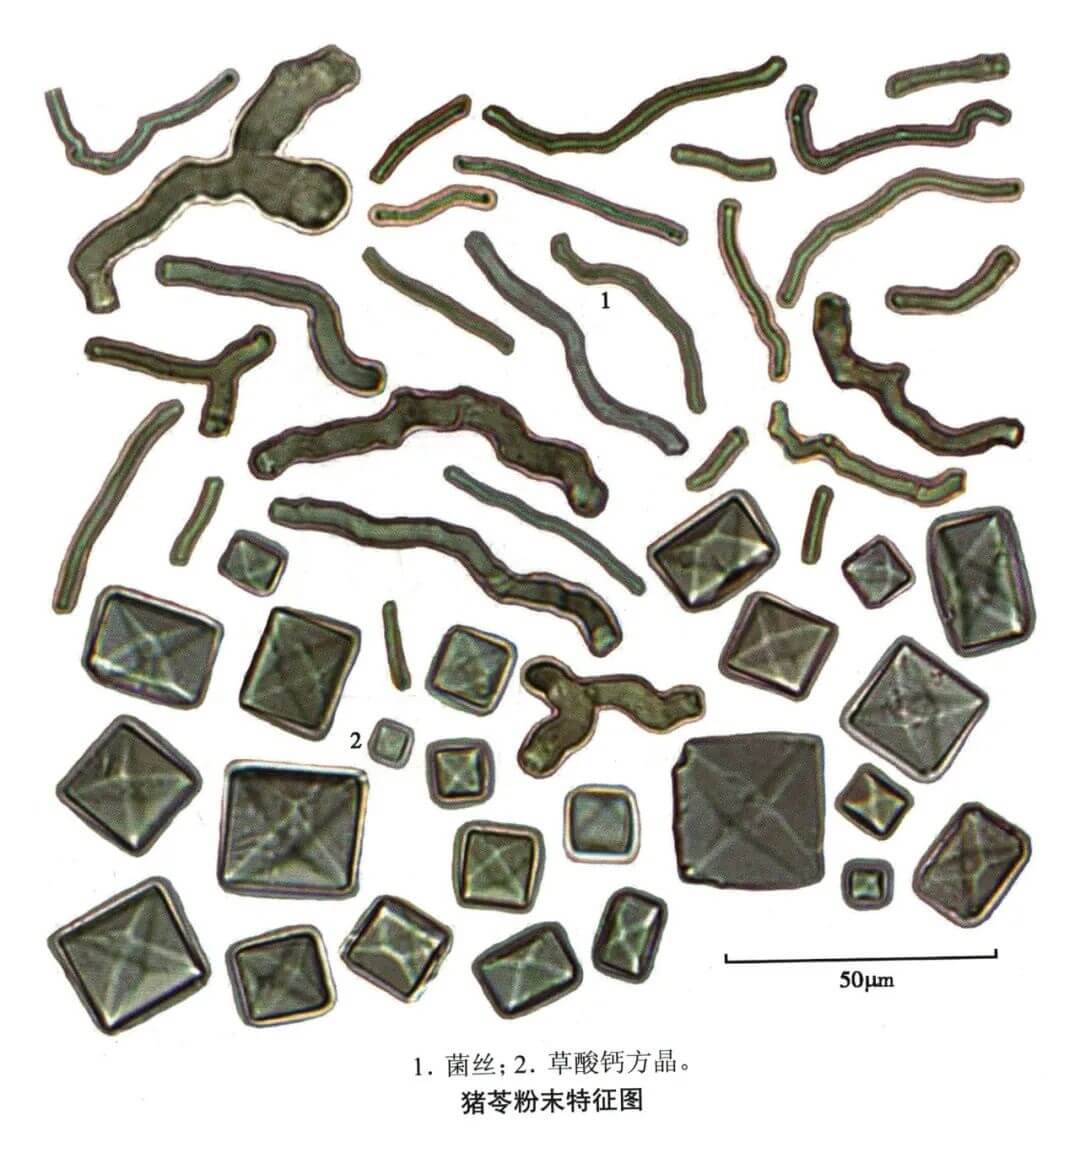

猪苓

| 猪苓 |

|---|

| 【参考文献】 《中药鉴定学》(康廷国主编) |

| 【显微鉴别】 粉末灰黄白色。菌丝团大多无色(内部菌丝),少数棕色(外层菌丝)。散在的菌丝细长、弯曲,直径2~ 10um,有的可见横隔,有分枝及结节状膨大部分。草酸钙结晶呈正八面体形、规则的双锥八面体形或不规则多面体,直径3 ~32 ~ 60μm,长至68μm,有时数个结晶集合。 |

| 【显微重点】 草酸钙结晶、菌丝。 |

| 【图谱来源】 《中药成方制剂显微图典》 |